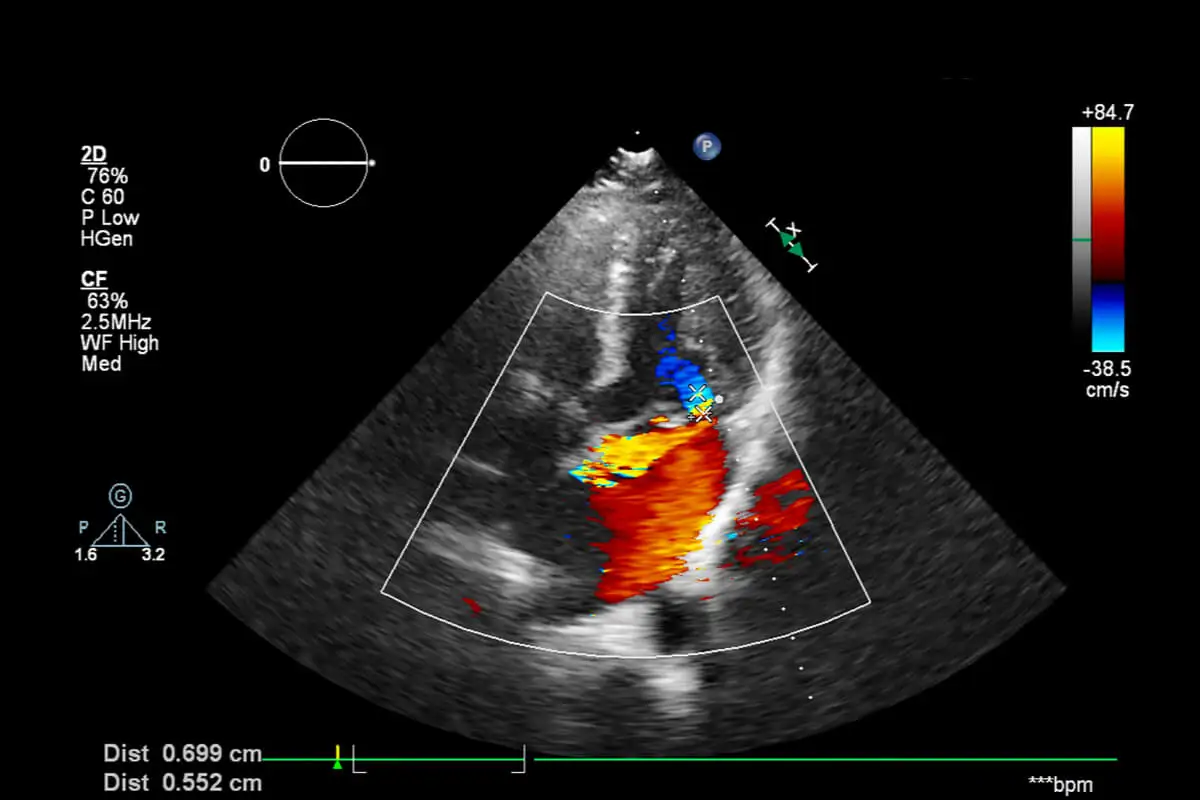

Jak już wspomnieliśmy, echokardiografia płodu to nieinwazyjna metoda obrazowania serca dziecka. Procedura daje dwu- i trójwymiarowy obraz 4 komór serca i dróg odpływowych. Ponadto, dzięki efektowi spektralnego i kolorowego Dopplera pozwala na ocenę przepływów krwi.

- EchoDoppler: wykorzystując efekt fizyczny, urządzenie mierzy prędkość, z jaką krew przepływa z jednej komory do drugiej i do naczyń. Dzięki temu możliwa jest ocena dynamiki przepływu płynu między różnymi częściami serca oraz funkcjonowania zastawek w czasie rzeczywistym. Według ekspertów jest to jedna z analiz, o które prosi się prawie zawsze w kontekście ciąży wysokiego ryzyka.